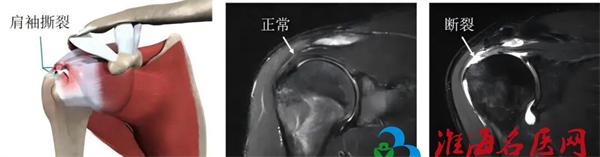

肩袖是包围我们肩关节的一组重要肌腱群,它们像“袖子”一样紧紧包裹着肩关节,负责肩关节的旋转、上举等各个方向的运动。由于退变、外伤或过度使用,这些肌腱可能发生撕裂,导致疼痛、无力、活动受限,这就是肩袖损伤。肩袖损伤不仅影响日常生活,还可能对工作造成严重影响。

以往,治疗肩袖损伤往往需要大面积切开肩膀进行开放手术,这不仅创伤大、恢复慢,还可能留下明显的疤痕。如今,随着医疗技术的进步,关节镜下肩袖修补术已成为主流和首选方法。这项技术仅需在肩部开3-4个如“钥匙孔”般微小的切口(约1厘米),然后伸入高清微型摄像头(关节镜)和精密手术器械,医生通过监视器放大清晰的影像进行操作,精准地对撕裂的肌腱进行修复和固定。

视野清晰,处理精准。 高清镜头可将关节内结构放大数十倍,使手术视野更清晰,能发现X光、MRI难以显示的隐匿损伤,并进行精准修复。